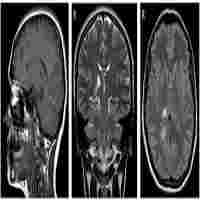

| Description | Residual effects of stroke include well-documented functional limitations and high prevalence of depression. Repetitive transcranial magnetic stimulation (rTMS) and aerobic exercise (AEx) are established techniques that improve depressive symptoms, but a combination of the two has yet to be reported. The purpose of this case series is to examine the safety, feasibility, and impact of combined rTMS and AEx on post-stroke depression and functional mobility. Three participants with a history of stroke and at least mild depressive symptoms (Patient Health Questionare-9 ≥5). Both rTMS and AEx were completed 3 times/week for 8-weeks. rTMS was applied to the left dorsolateral prefrontal cortex, 5000 pulses/session at 10 Hz, at an intensity of 120% of resting motor threshold. AEx consisted of 40 min of treadmill walking at 50–70% of heart rate reserve. Depressive symptoms improved in all three participants, with all demonstrating response (≥50% improvement in symptoms) and likely remission. All participants improved their Six Minute Walk Test distance and Participants 1 and 2 also improved Berg Balance Scale scores. Participants 1 and 3 improved overground walking speeds. No serious adverse events occurred with the application of rTMS or AEx and the participants' subjective reports indicated positive responses. Adherence rate for both rTMS and AEx was 98%. Combined treatment of rTMS and AEx appears safe, feasible, and tolerable in individuals with a history of stroke and at least mild depressive symptoms. All participants had good compliance and demonstrated improvements in both depressive symptoms and walking capacity. |